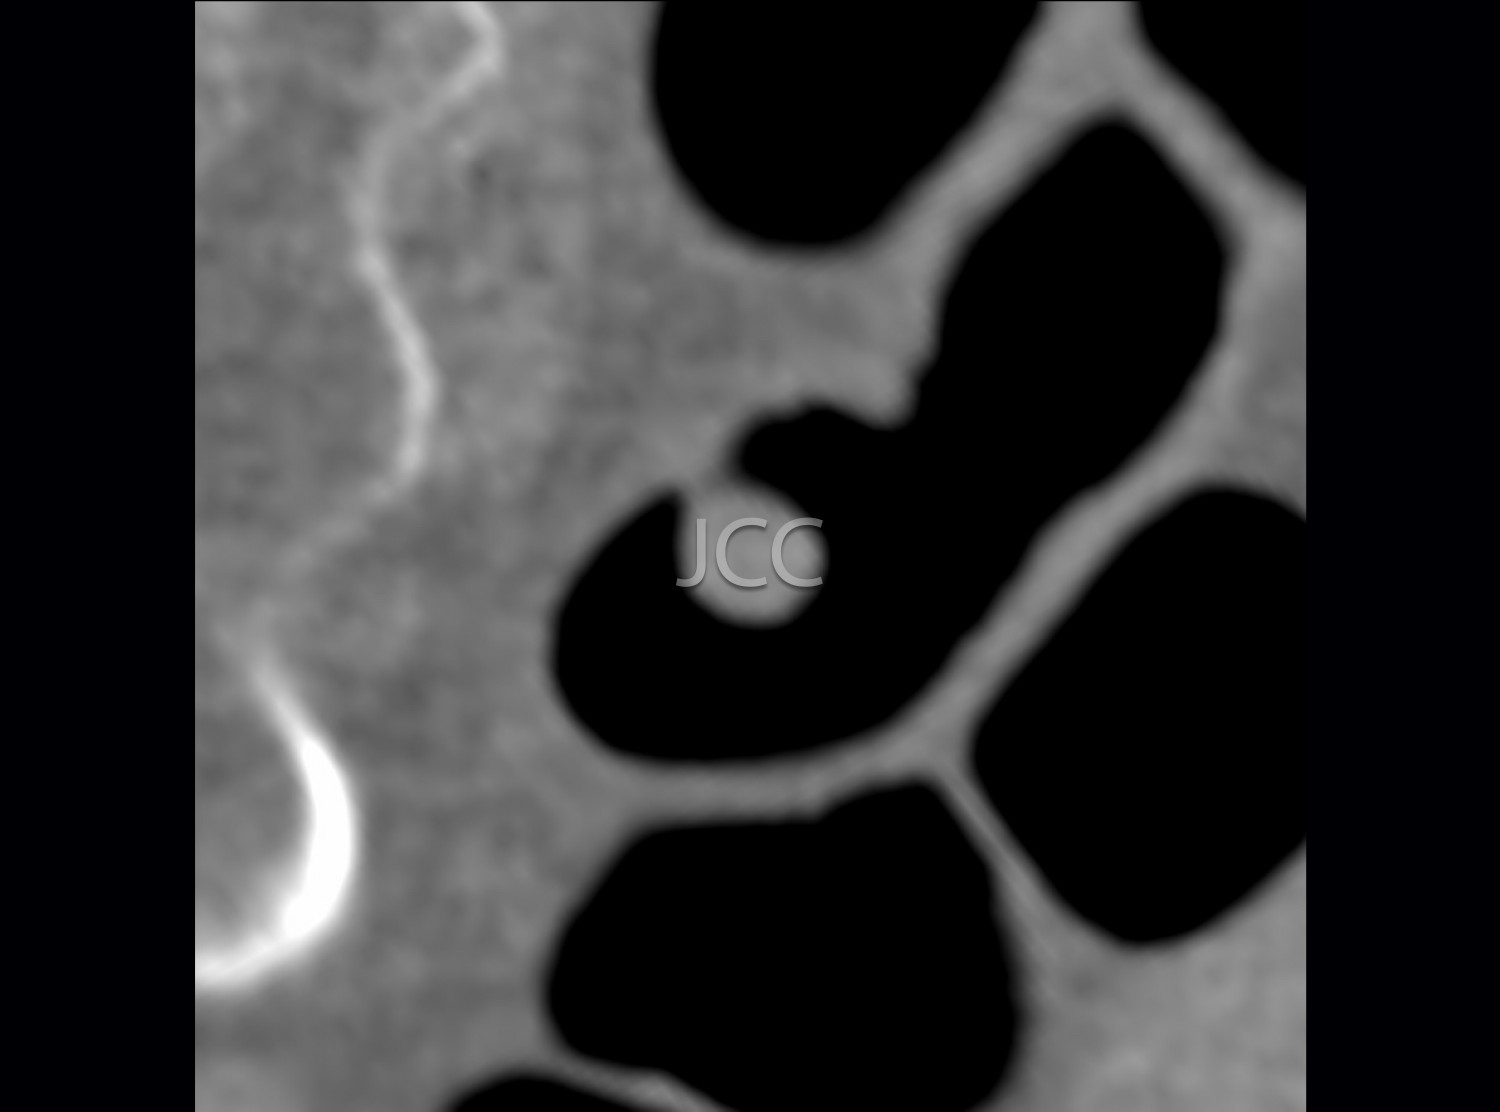

• Colonoscopia virtual por TC